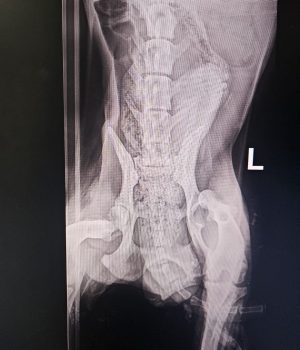

Seine Verletzungen waren schwer: mehrere Brüche der hinteren Gliedmaßen, schlechte Blutwerte und massive Verletzungen im Gesichtsbereich.

Inzwischen hat er zwei schwere Operationen an den hinteren Beinen sowie eine aufwendige Gesichtsrekonstruktion erstaunlich gut überstanden.